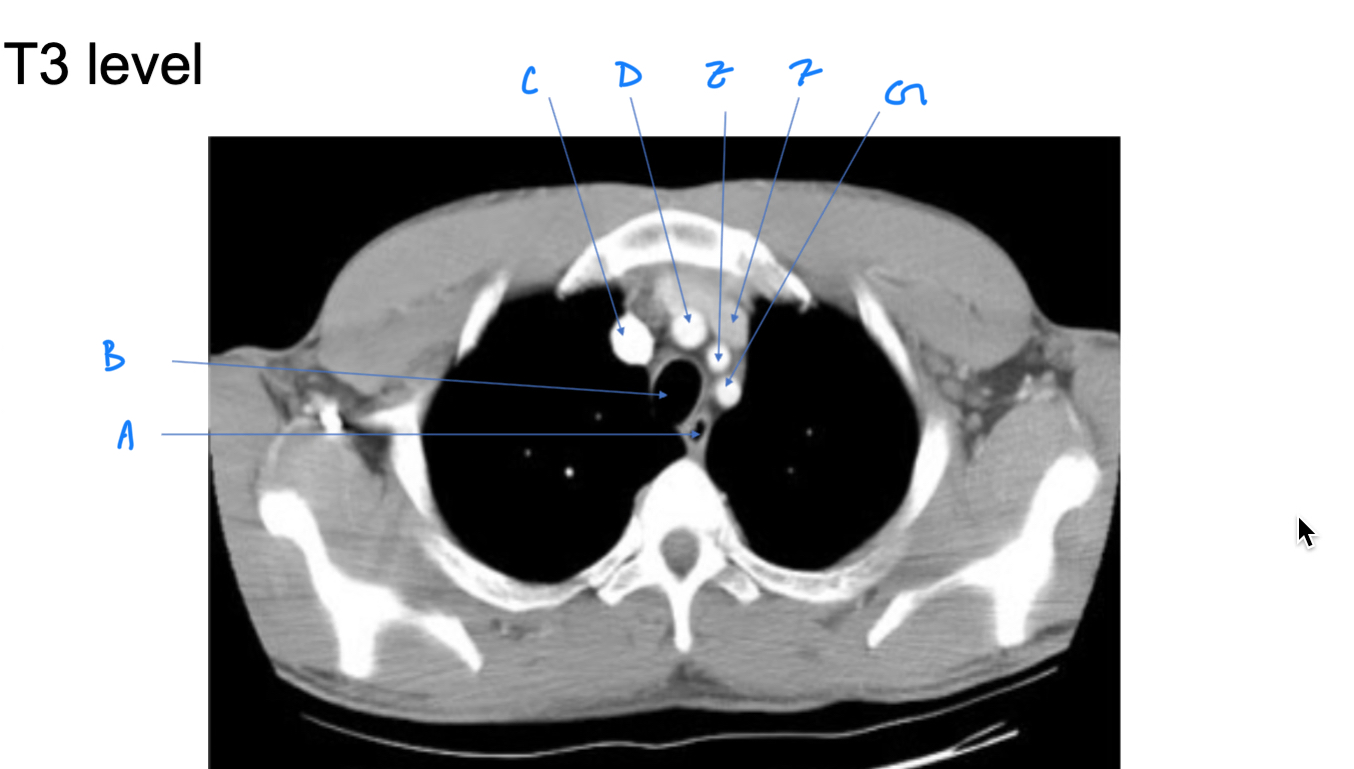

Esophagus

A. Identify

Trachea

B. Identify

R Brachiocephalic v.

C. Identify

Brachiocephalic trunk

D. Identify

L CCA

E. Identify

L Brachiocephalic v.

F. Identify

L Subclavian a.

G. Identify